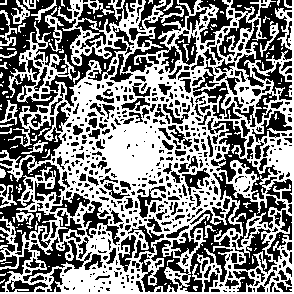

As it was noticed Fig.2(d) is example of low accuracy segmentation. The highly contrast cell core on this image attracts attention, while cell body and boundaries remains shattered. This contrast difference caused by cell morphology since cell itself has no more lens shape and changes to sombrero-hat shape affecting on contrast distribution. Fig.6 demonstrate changes of cell image during processing. As it seen there is high contrast core(actual cell nuclei zone) and almost invisible by eye body of cell with contrast same as in background when it seen by eye. After filtration with G-neighbor and Kuwahara it is appear to became more contrast. However because of values for binarization applied globally for rest of images in sequence it produce false negative recognition 7.

Figure 6: Contrast enhancement as result of filter applying on images of Frame 15.